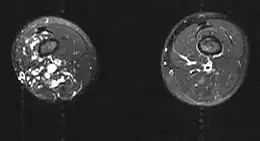

Le syndrome de Klippel-Trenaunay est un syndrome congénital[1] apparaissant dans le développement embryonnaire et qui se caractérise par l'association d'une hypertrophie des tissus osseux et mous, d'angiomes cutanés et de veines variqueuses.

L'atteinte est le plus souvent limitée à un seul membre. Le pronostic est variable et dépend de l'extension de la malformation et des organes touchés. C'est une malformation rare, plus de 1 000 cas ont été répertoriés. Sporadique le plus souvent, on retrouve parfois une transmission autosomique dominante. L'étiologie est inconnue. Le traitement reste symptomatique et il n'existe pas encore de traitement curatif. La prise en charge est multidisciplinaire. Les angiomes cutanés peuvent être traités au laser, les varices et l'inégalité de longueur des membres peuvent bénéficier d'une prise en charge chirurgicale, les lymphœdèmes des membres inférieurs de bas de contention.